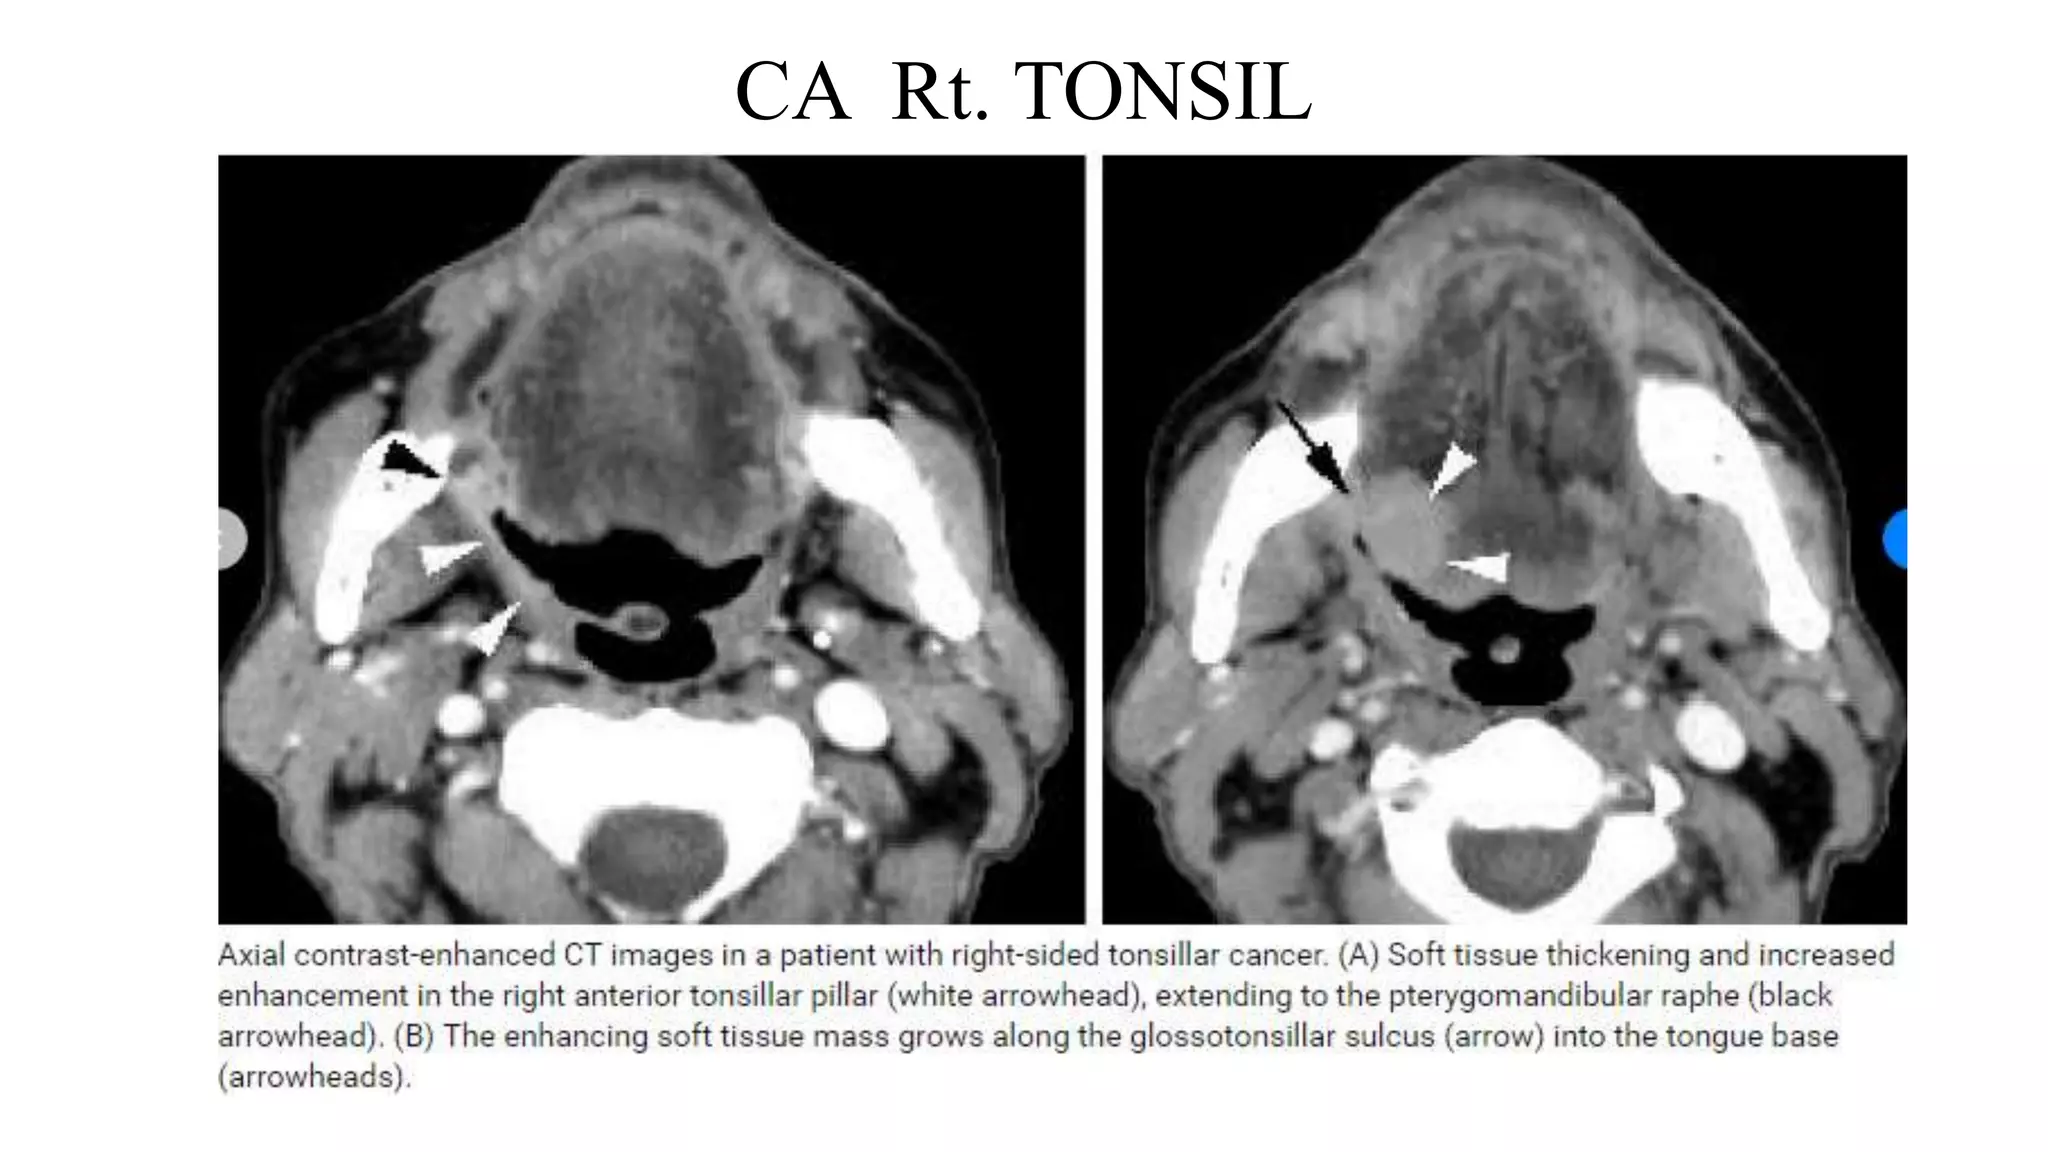

CA Rt. TONSIL

An MRI image showing right tonsillar growth

associated with Rt cervical adenopathy.

PET CT of the same patient

CARCINOMA TONSIL